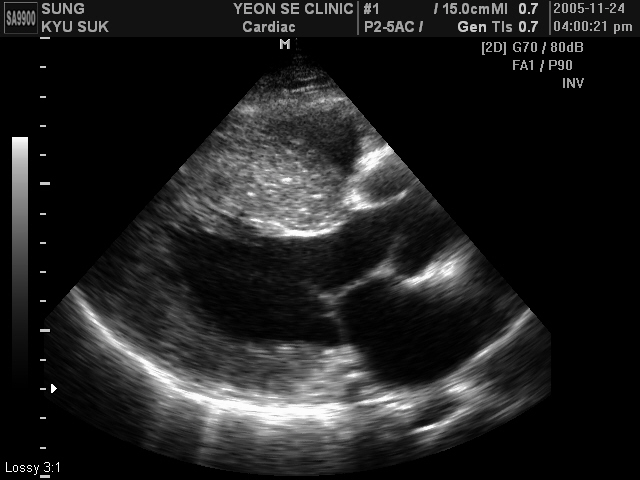

Ultrasonographic data of our patients

Other